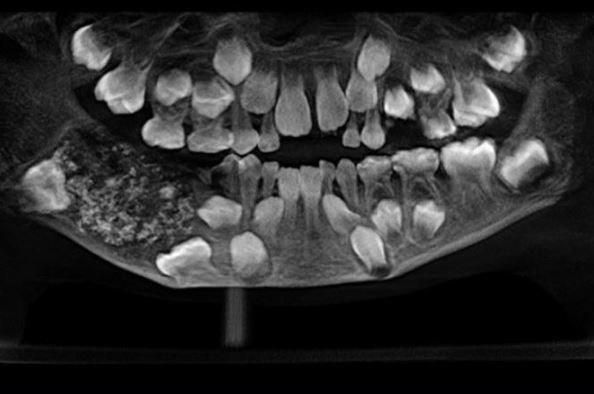

A team of doctors at the Oral and Maxillofacial Pathology headed by Dr. Prathiba Ramani conducted a scan and spotted a sac embedded in his lower jaw filled with “abnormal teeth.”

“There were a total of 526 teeth ranging from 0.1 millimeters (.004 inches) to 15 millimeters (0.6 inches). Even the smallest piece had a crown, root and enamel coat indicating it was a tooth,” Dr. Prathiba Ramani is quoted as saying.